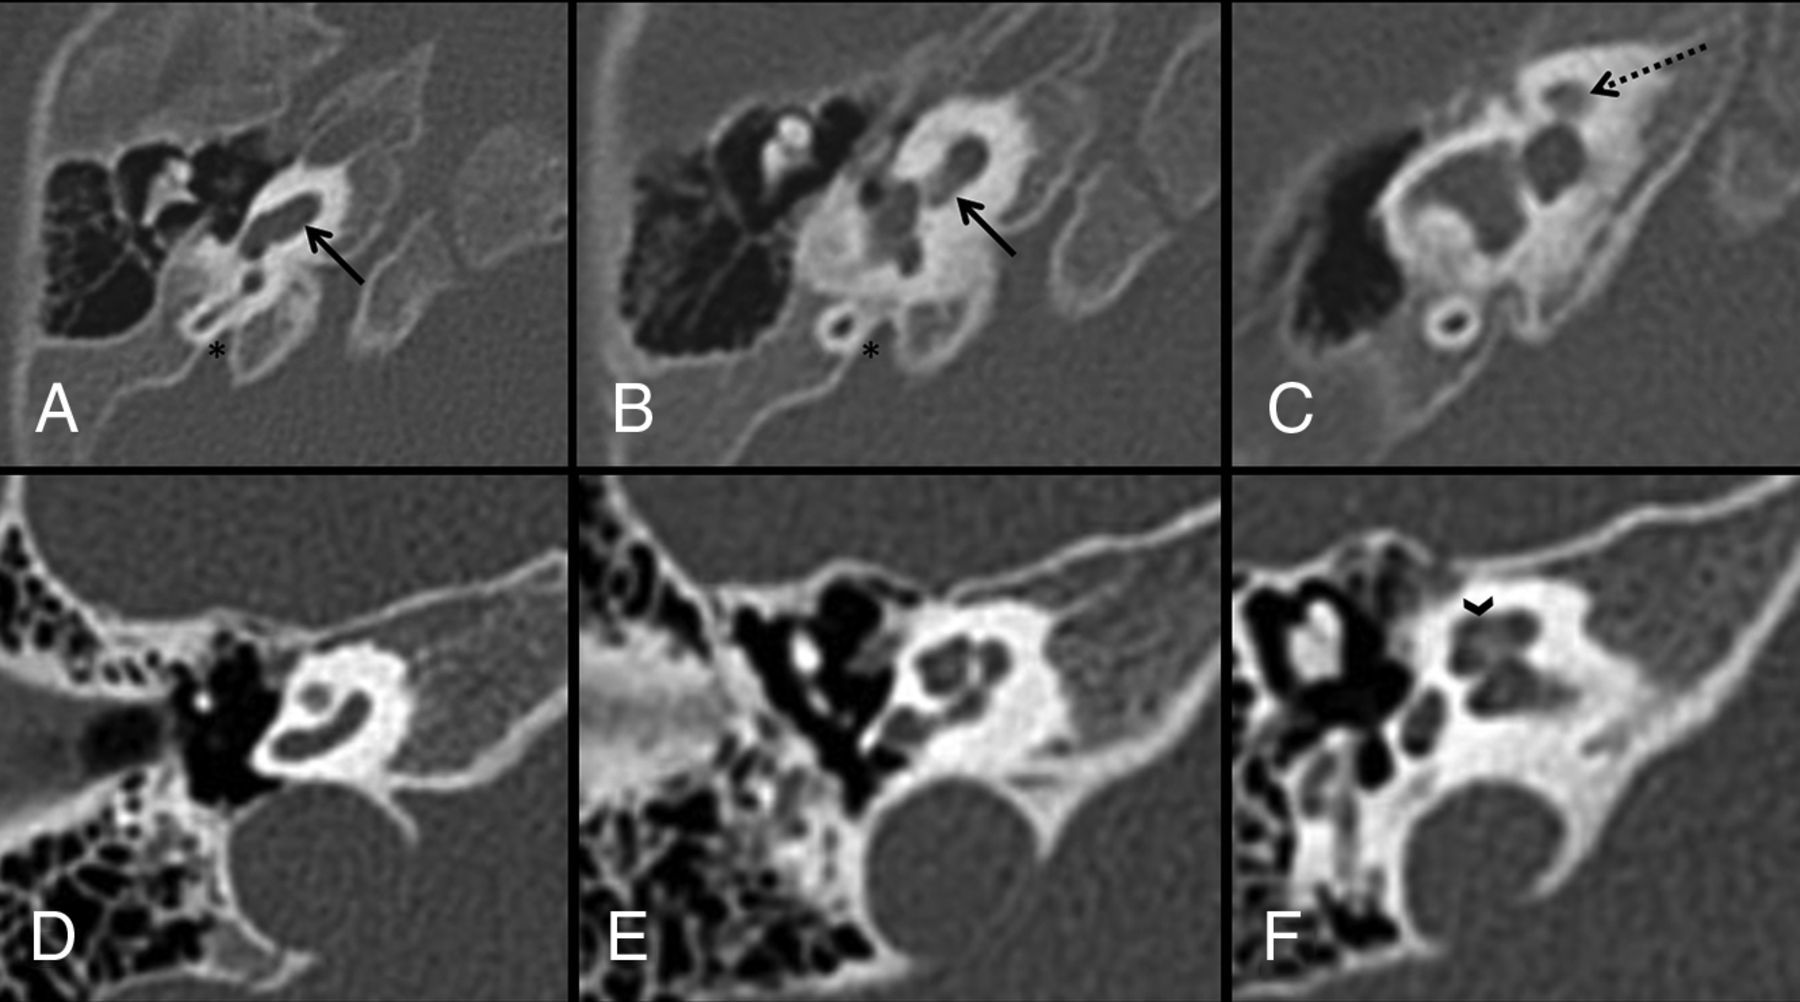

The most frequent finding was characteristic cochlear hypoplasia with a normal basal turn and extremely hypoplastic upper turns that appeared offset anteriorly with respect to the basal turn. Given the normal basal turn, this was classified as a CH type 4 (Figs 1 and 2).

Axial CT with thin bone reformats in patient 1. The WWS phenotype and POMT1 variant (A, B, and C) show a characteristic CH4 AOUT with a normal basal turn (arrows in A and B) and a very hypoplastic and anteromedially displaced upper part of the cochlea (dashed arrow in C). The abnormality was symmetric on both sides. Note the normal appearance of the semicircular canals and vestibule. The vestibular aqueducts (asterisk in A and B), despite looking slightly enlarged on subjective analysis, were within normal limits when measured. A normal cochlea for comparison (D, E, and F) shows well-developed middle and apical turns (arrowhead in F).

This morphology was found in 13/24 patients. Most interestingly, the pronounced CH4 with an anterior offset of the upper turn (CH4 AOUT) was present in 12/13 of patients with WWS but only 1/11 of the remaining phenotypes, a patient with MEB. The remaining patient with WWS also had a small cochlea with a normal basal turn (CH4)6,12 but with better developed upper turns, similar to the other less severe CH4 found in some of the patients with MEB and FCMD (Fig 3). Among the MEB phenotypes, 5/8 patients had normal cochleae, 1/8 had CH4 AOUT, and 2/8 showed a less severe form of CH4. Patients with FCMD had normal cochleae in 2/3 cases, while 1 subject had a less severe form of CH4. In all patients, we found that the vestibules and semicircular canals were normal (Fig 2). The vestibulocochlear nerves were bilaterally present in all cases (on axial T2 images).